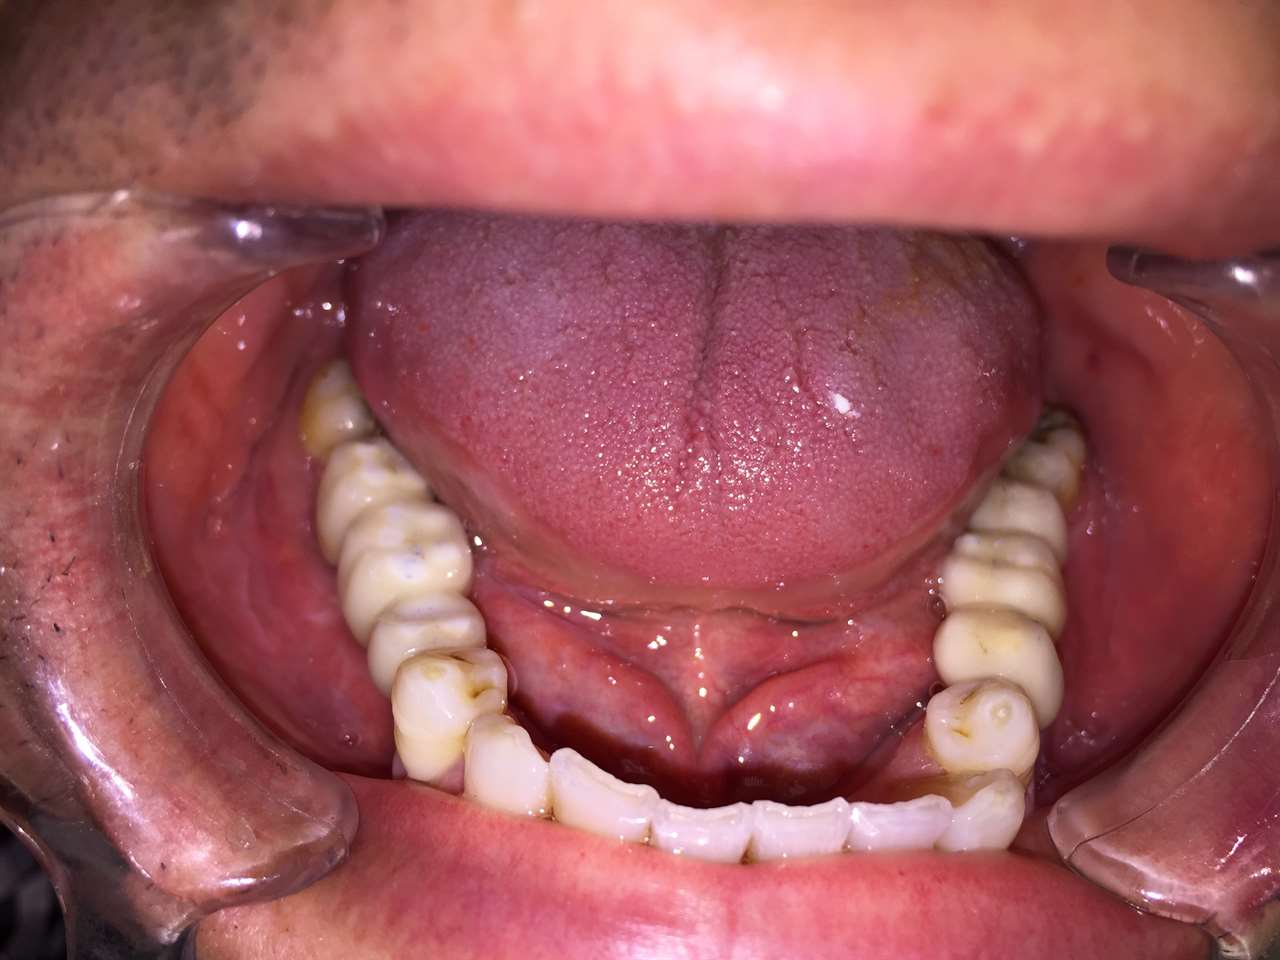

Alsó állcsont teljes rehabilitációja 72 óra alatt, azonnal terhelhető implantátumokkal súlyos paradontitisben szenvedő dohányzó páciens esetében. Az alsó állcsont fogai mind mozogtak az előrehaladott fogágypusztulás miatt.

A fogakat eltávolítottuk, a gyulladt, fertőzött csontot kitakarítottuk, kifertőtlenítettük, majd azonnal implantáltunk.

Svájci, IHDE márkájú, azonnal terhelhető implantátumokat helyzetünk be, és ezekre harmadnapra rögzített, hosszútávú, fémvázas, esztétikus műanyaggal leplezett hidat ragasztottunk be.

Ezt az ideiglenes hidat a sebek gyógyulása miatt használjuk, de tartóssága miatt véglegesként is használható. A legtöbb esetben, ahogy itt is, 6 hónap múlva porcelán hídra cseréljük, a teljes gyógyulás után.